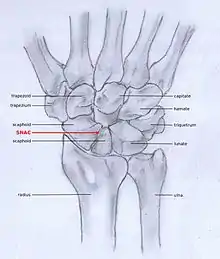

Osteoarthritis of the wrist can be idiopathic, but it is mostly seen as a post-traumatic condition.[1][3] There are different types of post-traumatic osteoarthritis. Scapholunate advanced collapse (SLAC) is the most common form, followed by scaphoid non-union advanced collapse (SNAC).[4] Other post-traumatic causes such as intra-articular fractures of the distal radius or ulna can also lead to wrist osteoarthritis, but are less common.

SLAC and SNAC are two patterns of wrist osteoarthritis, following predictable patterns depending on the type of underlying injury. SLAC is caused by scapholunate ligament rupture, and SNAC is caused by a scaphoid fracture which does not heal and because of that will develop in a non-union fracture. SLAC is more common than SNAC; 55% of the patients with wrist osteoarthritis has a SLAC wrist.[4]

SNAC

Scaphoid non-union fractures changes scaphoid bone shape, which leads to abnormal joint kinematics. Due to lack of stability from the distorted scaphoid, a DISI can be developed.[3][6] Scaphoid Non-union Advanced collapse (SNAC) is the pattern of osteoarthritis that eventually develops by this process.